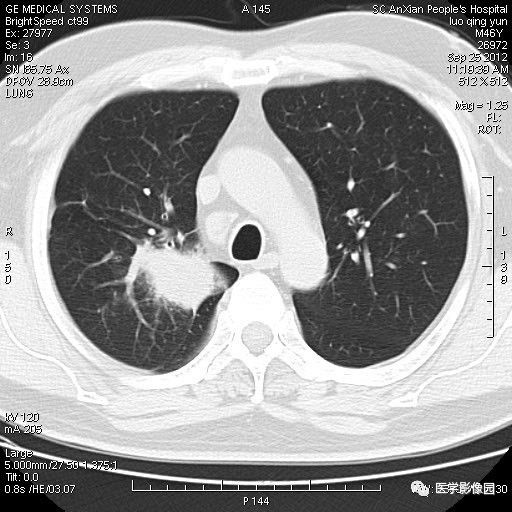

【病例】右上肺炎性假瘤1例CT影像表现

患者男性,46岁,临床未提供病史。

影像学表现:右上肺见不规则团块状高密度阴影,略有分叶级毛刺,边缘模糊,邻近胸膜增厚,增强扫描呈轻中度强化。

诊断结果:右上肺炎性假瘤

本病影像学表现无绝对特征性。单发多见,多位于肺表浅部位,多呈圆形或椭圆形,直径多在2-5cm或更大;多有假包膜,边缘多清晰光整,有时也毛糙,并可有分叶或毛刺;邻近胸膜局限性增厚、牵拉,病灶边缘呈桃尖样突起即桃尖征(尖端指向胸膜);增强扫描多呈中度均匀强化,持续时间较长。亦可显著强化。